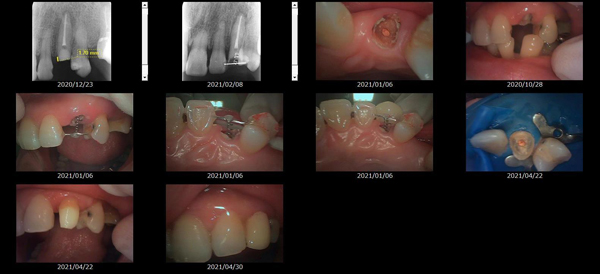

救歯MTM

虫歯が大きくて残せない歯、転倒などの事故により歯が根の深いとこで折れてしまったなどで、抜かざるを得ない歯を、骨の中に埋まっている健全な根を、骨の上に矯正的に引き上げることで、その歯を抜かず温存、救歯できる可能性のある治療方法です。

①健全な歯を、歯肉から見える位置にまで引き上げることで

根の治療の成功率を上げることが出来る。唾液には沢山の細菌がいます。唾液が入らない環境での根の治療を(神経の治療)を行うことで神経の治療、根の治療の成功率は格段と上がります。

②骨の上にある歯と土台で支える被せもの製作できる。

被せものを土台だけに頼ることなく、引き上げた健全な歯でも支えることで、歯への被せ物がしっかりと装着できるようになる。

③抜かずに歯を活かすことで、隣の歯を削るブリッジやインプラントにしないで済むことがある。

歯を矯正的に引き上げることで、その歯を救歯できるだけでなく、隣の歯を削るなどの侵襲を回避できる場合がある。

症例